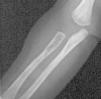

Ya en dicha unidad, con 2 meses de vida, el estudio realizado (ecografía abdominal, TC de cráneo, de región mastoidea y de tórax, así como biopsia de médula ósea) sigue sin evidenciar afectación sistémica hasta que al repetir una segunda serie ósea se descubre una lesión osteolítica en radio (fig. 1), la cual junto con la aparición de hipoproteinemia (2 g/dl), hizo considerar el grado de afectación sistémica tributario de iniciar tratamiento con quimioterapia (prednisona, vinblastina y metotrexato). Con ésta, la evolución clínica inicial es favorable, desapareciendo las lesiones cutáneas, cediendo la irritabilidad, tolerando la alimentación y ganando peso. Transcurridos casi 4 meses con tratamiento, fallece por afectación intercurrente aguda bronconeumónica no filiada (la familia no concedió la necropsia).

Figura 1. Lesión osteolítica en radio.